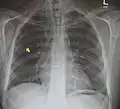

Pneumomediastinum is uncommon and occurs when air leaks into the mediastinum. The diagnosis can be confirmed via chest X-ray showing a radiolucent outline around the heart and mediastinum or via CT scanning of the thorax.

Pneumomediastinum and right sided pneumothorax post first rib fracture in a mountain biking accident. Pneumomediastinum and right sided pneumothorax post first rib fracture in a mountain biking accident.